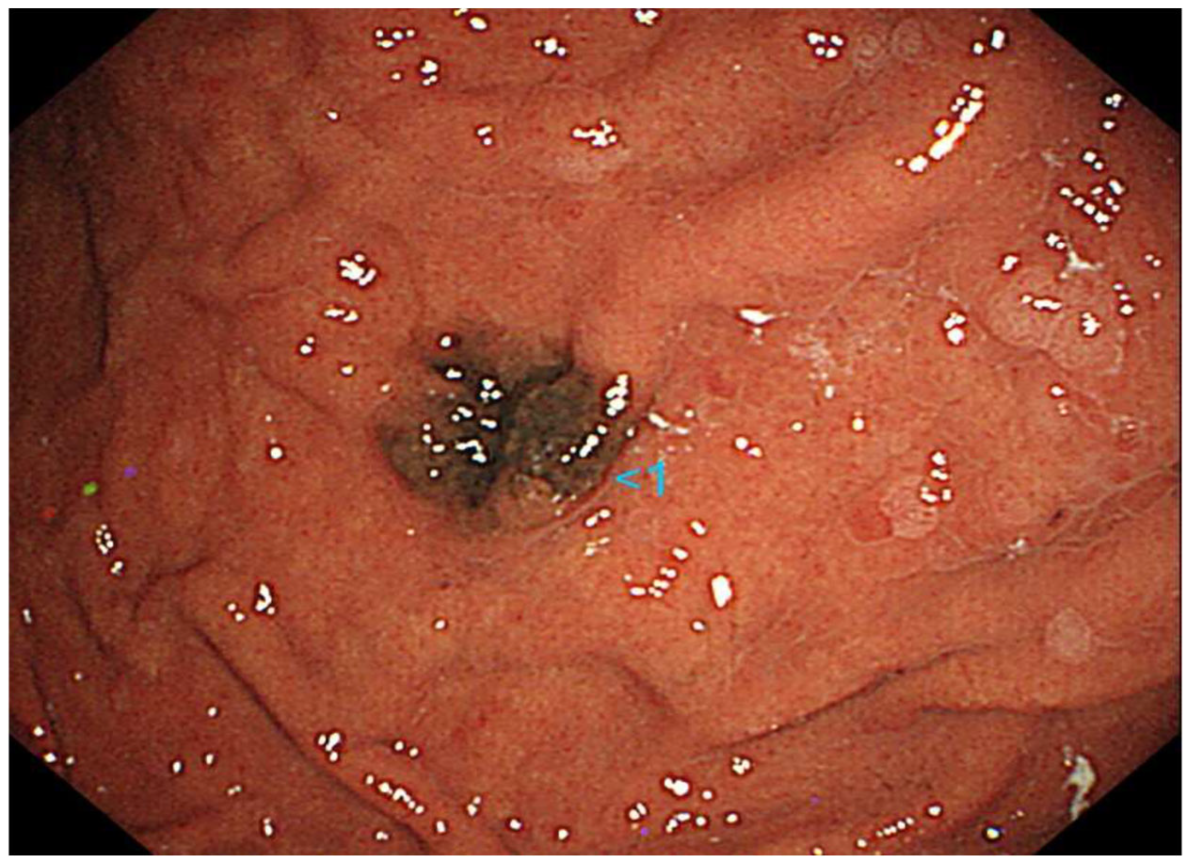

A 70-year-old Japanese woman was found to have a black lesion in her stomach during routine upper gastrointestinal endoscopy 3 years prior to her first dermatological consultation (Figure 1).

Figure 1.

Upper gastrointestinal endoscopy reveals a black lesion in the stomach.